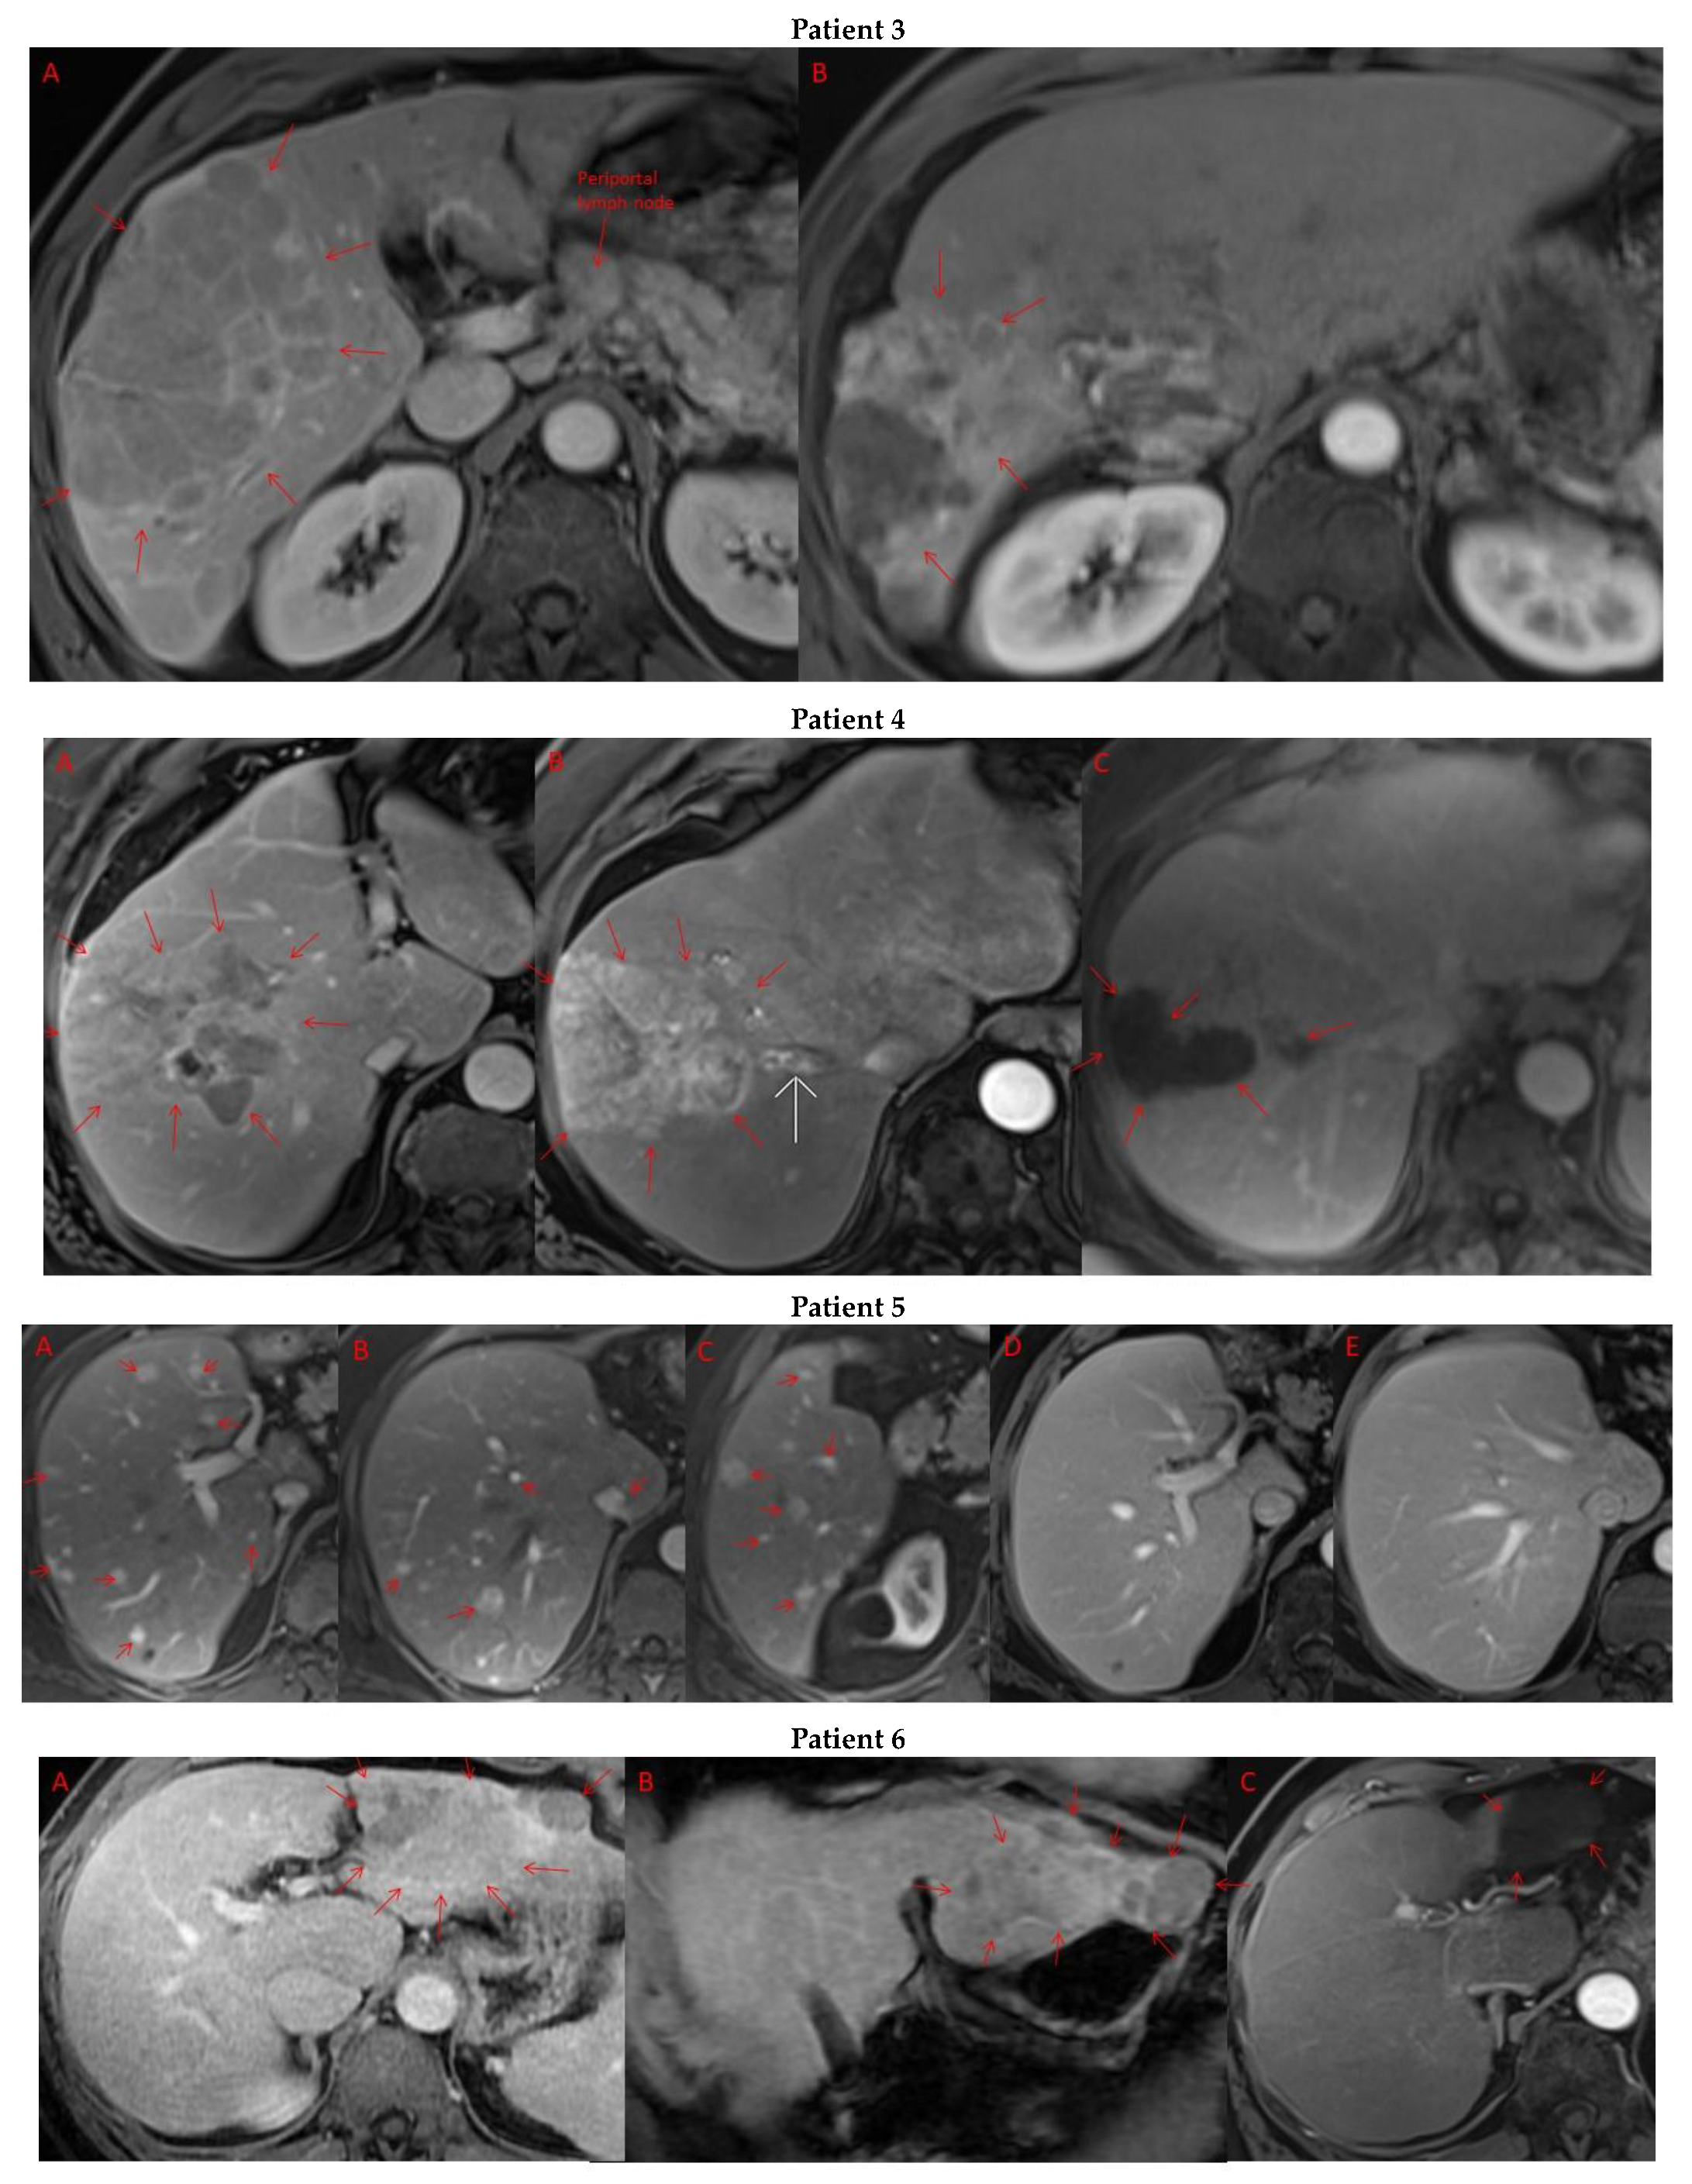

Pre- and post-treatment imaging for all exceptional responders is provided (Figure 3).

Figure 3.

Imaging findings in patients (n = 11) with complete response to neoadjuvant immunotherapy. Cross-sectional imaging for each patient with complete response to immunotherapy. Images represent the scan most recently taken prior to beginning the course of neoadjuvant treatment and the scan taken most recently after completion. (Patient 1) MRI showing large pre-treatment infiltrative tumor (A) followed by decrease in size from 10 cm to 5.6 cm status post 15 cycles of immunotherapy (B). (Patient 2) Large ill-defined 11cm tumor at diagnosis (A) followed by decrease in size to 3.6cm after 1 cycle Atezolizumab (B). (Patient 3) 13.3 cm mass with periportal lymphadenopathy (A) and subsequent decrease in size to 6.9 cm after 5 cycles of immunotherapy+1 round Y90 (B). (Patient 4) 8.1 cm mass in segment VIII with extension to right hepatic vein (A,B), and post-treatment tumor shrinkage after 11 cycles immunotherapy and locoregional treatment (C). (Patient 5) Recurrent scattered HCC lesions after previous resection (A–C). Near complete resolution after 4 cycles of immunotherapy and 1 Y90 (D,E). (Patient 6) 8 cm mass in segment II/III with portal vein invasion (A,B) and complete resolution after 22 cycles immunotherapy, Y90 and SBRT (C). (Patient 7) Infiltrative 20.3 cm mass in the left lobe with extensive tumor-in-vein in portal venous system (A,B) followed by complete resolution on 20 cycles immunotherapy, locoregional treatment and SBRT (C). (Patient 8). 7.1 cm mass in the right lobe (A,B) with reduction to 1.7 cm after 31 cycles immunotherapy (C). (Patient 9) 14.7 cm mass in the right hepatic lobe (A,B) shrinking to 5.8 cm after treatment (C,D). (Patient 10) Patient post-partial resection of segment IV/V for HCC with recurrence demonstrating 3.2 cm segment V/VIII lesion (A), a 4 cm lesion in the Right lower lobe (B) and a peritoneal metastasis (C). After treatment with 9 cycles immunotherapy + multiply Y90 treatments tumor size shrunk significantly (D–F). (Patient 11) Patient post-right hepatectomy for HCC with multiple diffuse recurrent nodules in the liver with largest measuring 2.6 cm (A,B). Post treatment imaging showing no evidence of disease (C).